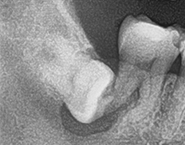

外面拔時易斷裂於骨頭內而難以取出